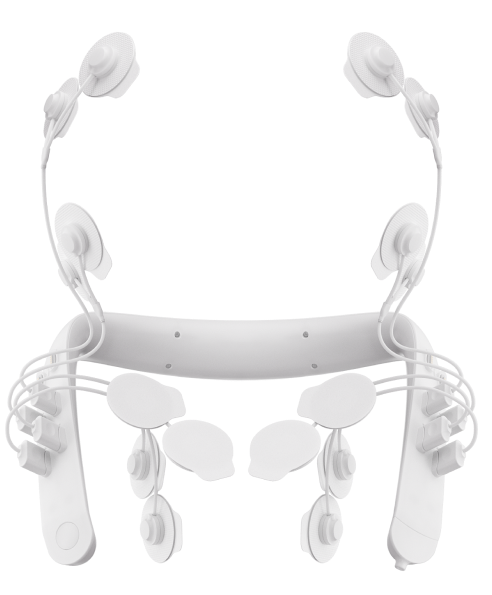

Basic diagnostic module

Enables the collection of lower jaw movement data. Registers any abnormalities related to occlusion or joint issues.

Using a myograph and TENS allows for a more detailed muscle analysis.